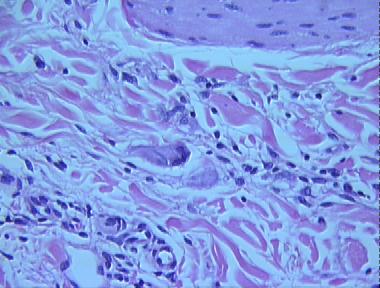

actinic granuloma

Histologic Features